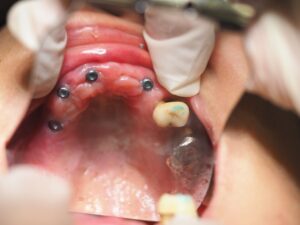

ろー提での顎の高さの確認。BTは初診時のスキャンデータでご本人の最初の顎位も確認。その後、アバットメント装着、テック装着。

仮歯ですが、かなり満足をされておりました。本物はまた後日載せます。

アバットメント

仮歯